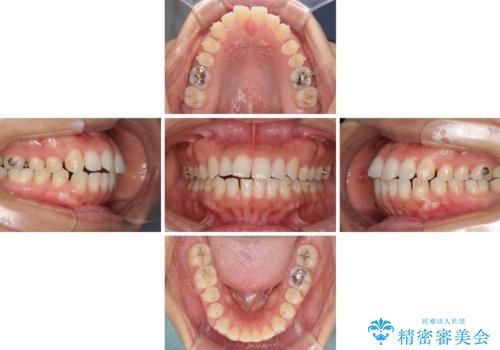

- 前歯の隙間と口元の突出感を気にして来院された患者様です。

嚥下時に舌を突出させる癖があり、成長期に下顎が有意に成長し、歯と歯の間に隙間ができてしまいました。

舌の癖を改善し、インビザラインにて治療を行うこととしました。